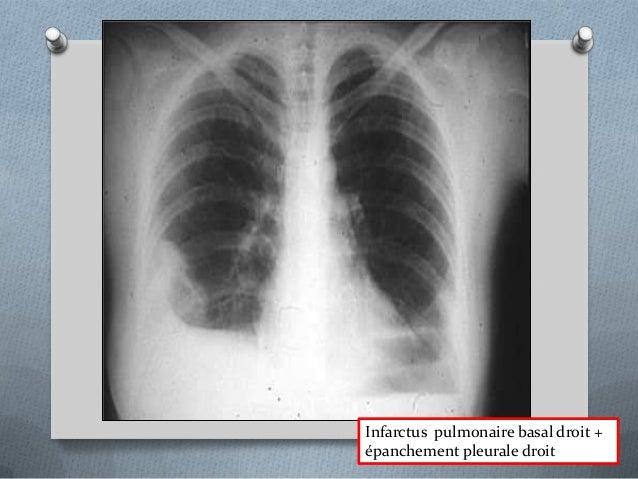

Aide au Codage CIM 10 embolie pulmonaire poumon CCAM et CIM10 en Français Site gratuit de codes CIM10 et CCAM, compatible AMELI, dédié au PMSI. Introduit un infarctus pulmonaire de la maladie La première raison est l'apparition de caillots sanguins dans les vaisseaux sanguins Lorsque le blocage de la lumière du vaisseau par un caillot de sang, une personne commence une attaque. Infarctus pulmonaire Image dœdème pulmonaire Les signaux pleuraux Comblement dun cul de sac pleural Épanchement scissural Ascension dune coupole diaphragmatique 2 Électrocardiogramme ECG normal 25 % des cas Tachycardie sinusale Déviation axiale droite , aspect S1 Q3.

1er épisode WhyDoc l'embolie pulmonaire Savezvous ce que c'est ?. Évolution de l’infarctus pulmonaire Résorption en 4 à 8 semaines « meltingsign » Image séquellaire linéaire, / rétractile 1 infarctus sub aigu à tendance rétractile 2 infarctus sub aigu atélectasie débutane et epanchement réactionnel. Embolie pulmonaire PDF Occlusion aiguë d’une artère pulmonaire ou d’une ou plusieurs branches des artères pulmonaires par un caillot fibrinocruorique migré d’une veine thrombosée, (située en général au niveau des membres inférieurs) Classe Cour de médecine PDF Module.